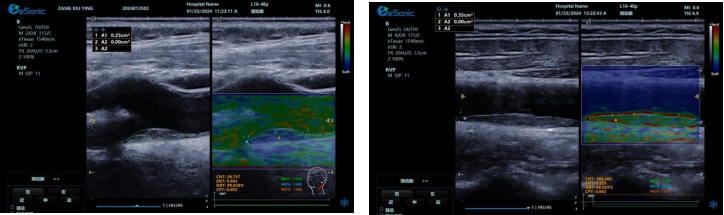

image.png

? 可视化,对颈动脉内膜和斑块实时弹性成像,彩色编码显示硬度,便于医生区分斑块类型。

? 定量测量方面,分析结果以kPam/s为单位测量颈动脉相关部位杨氏模量,毫米级分辨率显示微小病变,提供 20 余种参数综合评估斑块稳定性和血管硬化因测量取样范围可极度小甚至对于颈动脉内中膜硬度可定量测量,引发不同视角评价极早期动脉硬化评估,实属科研利器。

? 采用马赫圆锥脉冲激励技术,无需按压,减少检查者影响,帧频高、操作简便、耗时短。

RTSWE 是全球唯一的实时全幅全定量剪切波弹性成像系统,OmniSound?平台采集与显示帧频国际领先,对颈动脉结构定量分析和脑卒中早期预防意义重大。